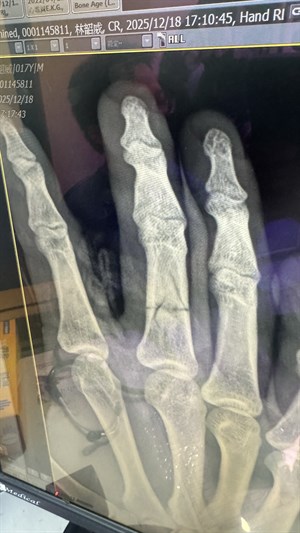

骨折